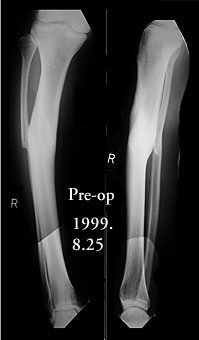

I am a 55-year-old male who suffered a compound fracture of the right tibia and fibula and extensive soft tissue damage, including vascular damage, from the impact of an automobile pinning the leg to a concrete wall in 1971. This occurred while I was a pedestrian. Emergency surgery restored circulation and set the tibia and fibula fragments with no internal fixation (due to concern about infection) and plaster cast immobilization. Later a bone graft was performed, and after physical therapy an apparently full recovery occurred, except a slight varus deformity, reduced vascularity, and reduced range of motion in the ankle. Over the years, the varus deformity worsened to 22 degrees and led to moderate osteoarthritis. To correct the deformity and straighten the tibia, an open-wedge osteotomy was performed in November 1999, with a bone graft from the other iliac crest. Plate fixation was used, as the bone was too hard to ream, so it was impossible to insert a pin. I have used the Exogen ultra-sound device every day since the surgery. Gradual improvement led to enhanced weight-bearing ability, and I have been walking with a cane since April 2000. Although X-rays taken June 16 showed no deformity, the varus deformity has recurred in the October 16 X-rays.

I am sending standing X-ray images of both knees for posting to the website. They show moderate osteoarthritis in the right knee and normal cartilage in the left knee. Knee pain was my initial complaint, and it was eventually diagnosed as resulting from the uneven pressure on the joint caused by the varus deformity. As to why the mild varus deformity of 1971 progressed to a 22-degree deformity in 1998, one answer I have received is that the 1971 fracture never healed properly.